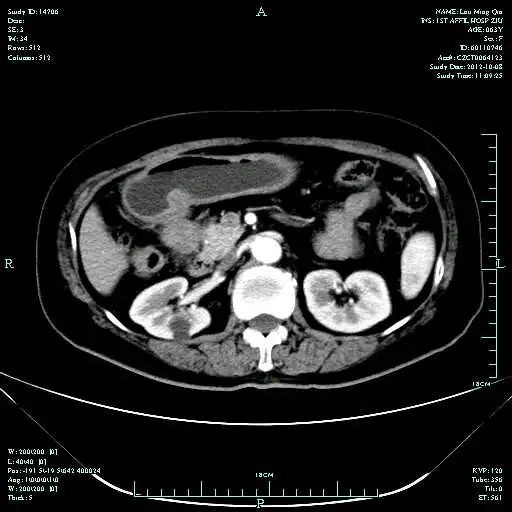

CT-T

CT-H1

MR-H1

影像学检查结果评估:cPD。

疗效评估:cPR

TOGA研究是第一个使用HER2抑制剂曲妥珠单抗治疗不能手术的局部晚期、复发或转移的HER2阳性胃癌患者的Ⅲ期临床研究。TOGA研究结果显示,IHC2+/FISH阳性或者IHC3+的患者与对照组相比,OS分别为16.0个月和11.8个月(HR为0.65)。曲妥珠单抗联合化疗显著提高了HER2阳性晚期转移性胃癌的治疗缓解率和总体生存率。2012年8月,曲妥珠单抗治疗HER2阳性转移性胃癌适应症在我国获批。对该患者进行病理切片会诊,幸运的是其HER2检测为阳性。随即进行靶向联合化疗治疗,三个周期后,肝转移灶消失,曲妥珠单抗治疗效果显著。九个周期的靶向治疗联合放化疗后,疗效评估cPR,随即行手术治疗。